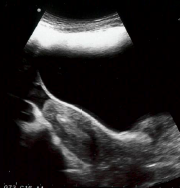

Het proces is te volgen doordat er gebruik wordt gemaakt van echoscopie via de buik.

De binnencatheter wordt in de buitencather geschoven en zo in de baarmoederholte gebracht door de arts. Het embryo wordt met een zeer kleine hoeveelheid vloeistof en lucht in de baarmoederholte gespoten. Deze kleine hoeveelheid lucht is waarneembaar voor u als luchtbellen op het echobeeld. Dit is de plek waartussen het embryo is teruggeplaatst.

Baarmoeder

Witte luchtbel is zichtbaar in de baarmoeder na plaatsing van het embryo